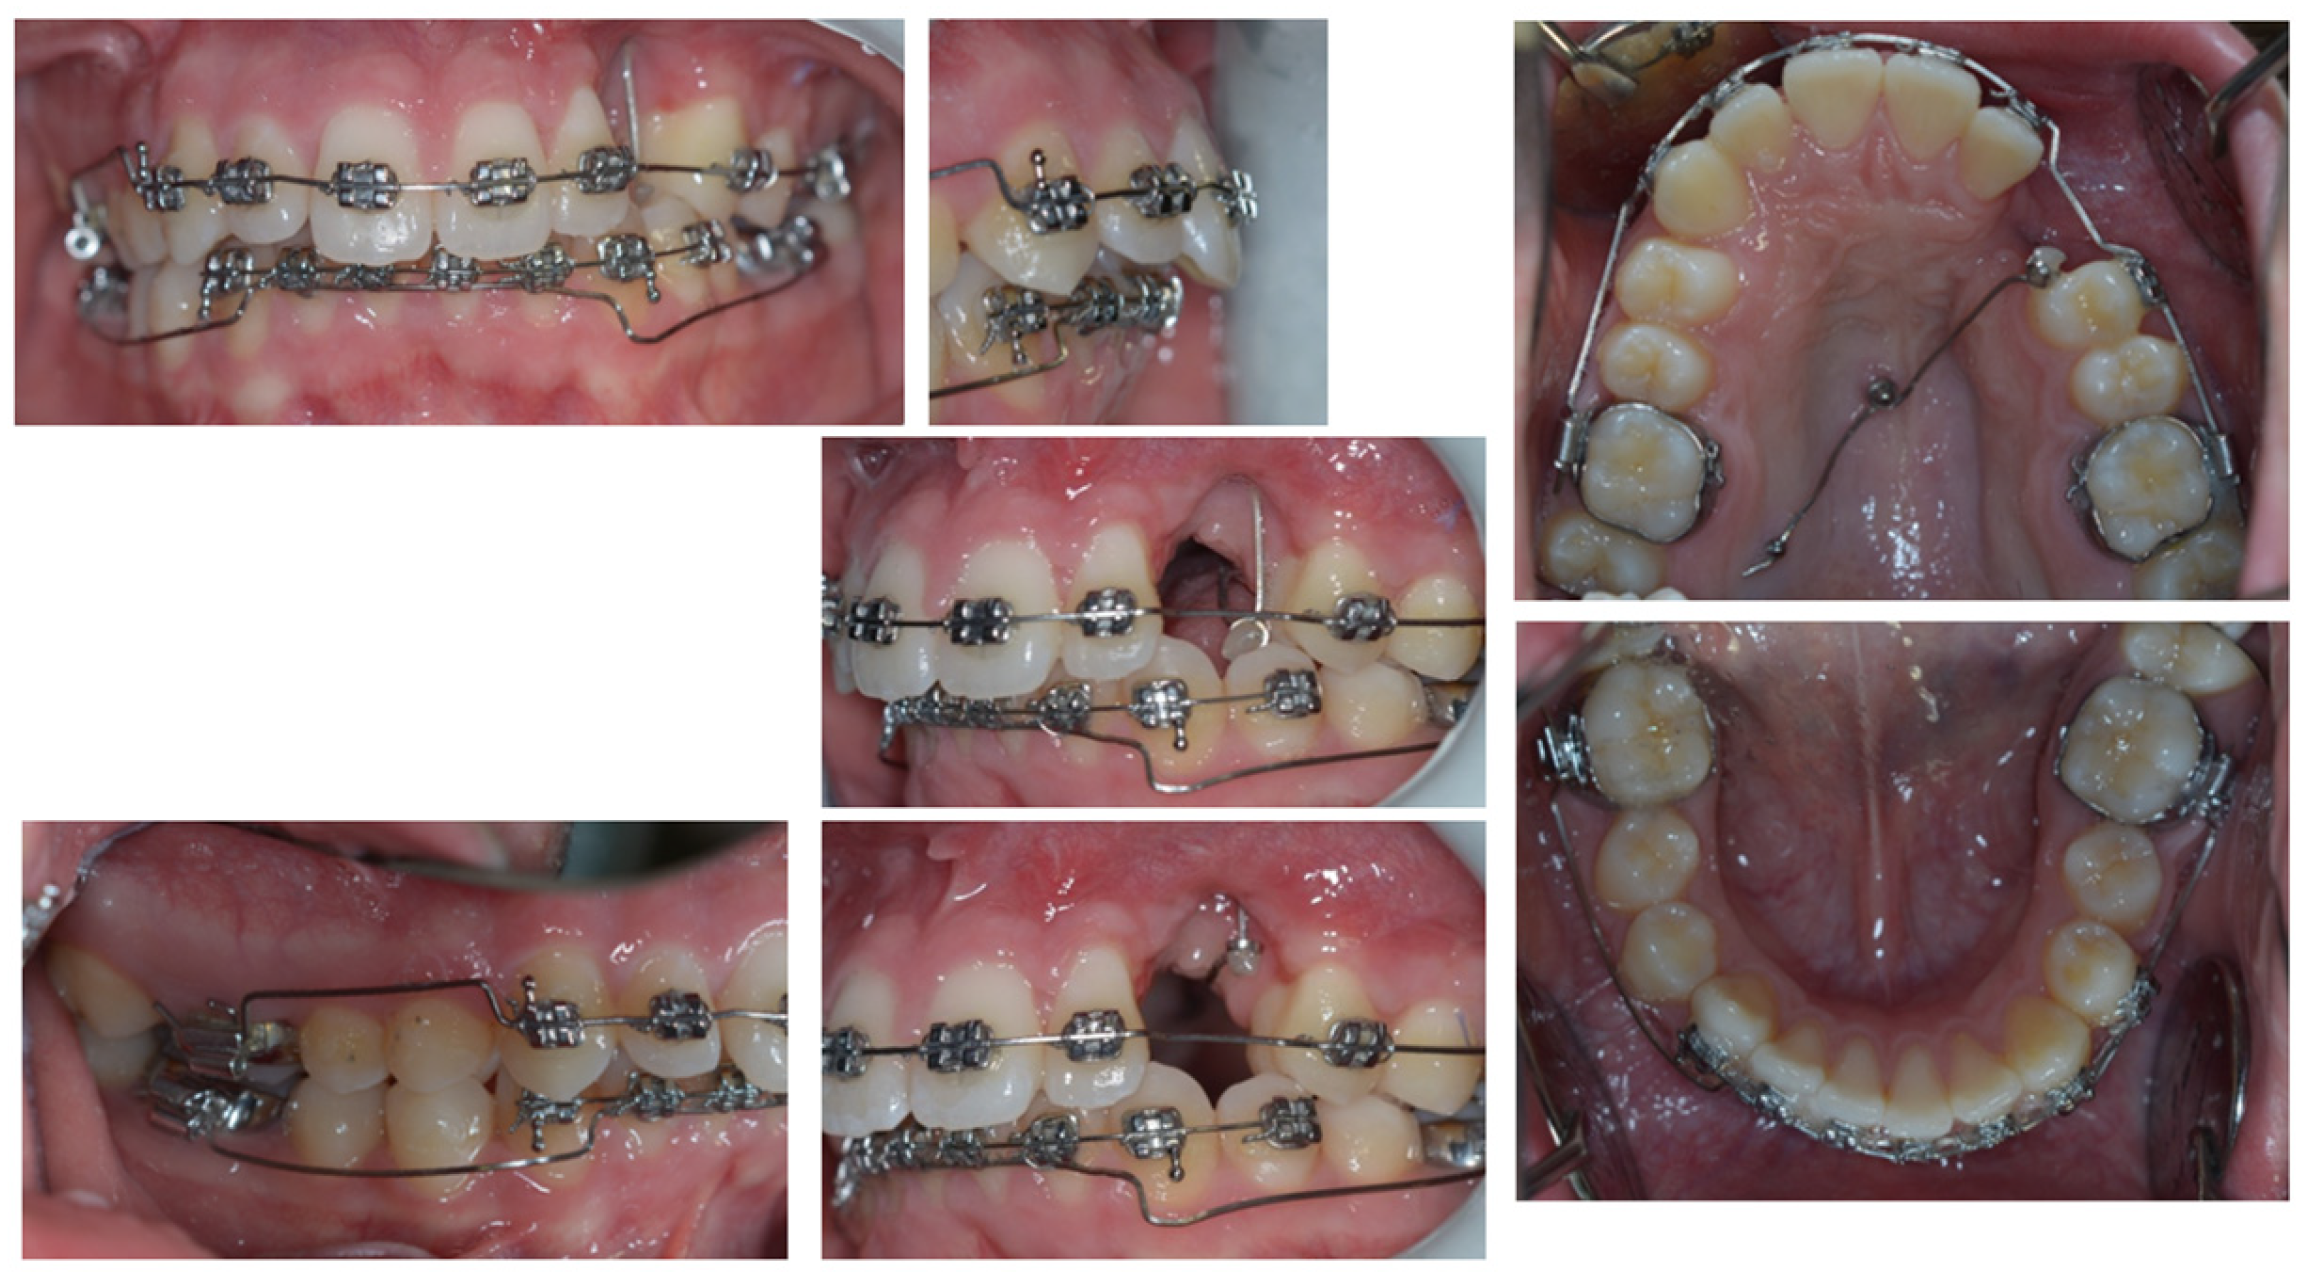

3. Therapeutic Interventions